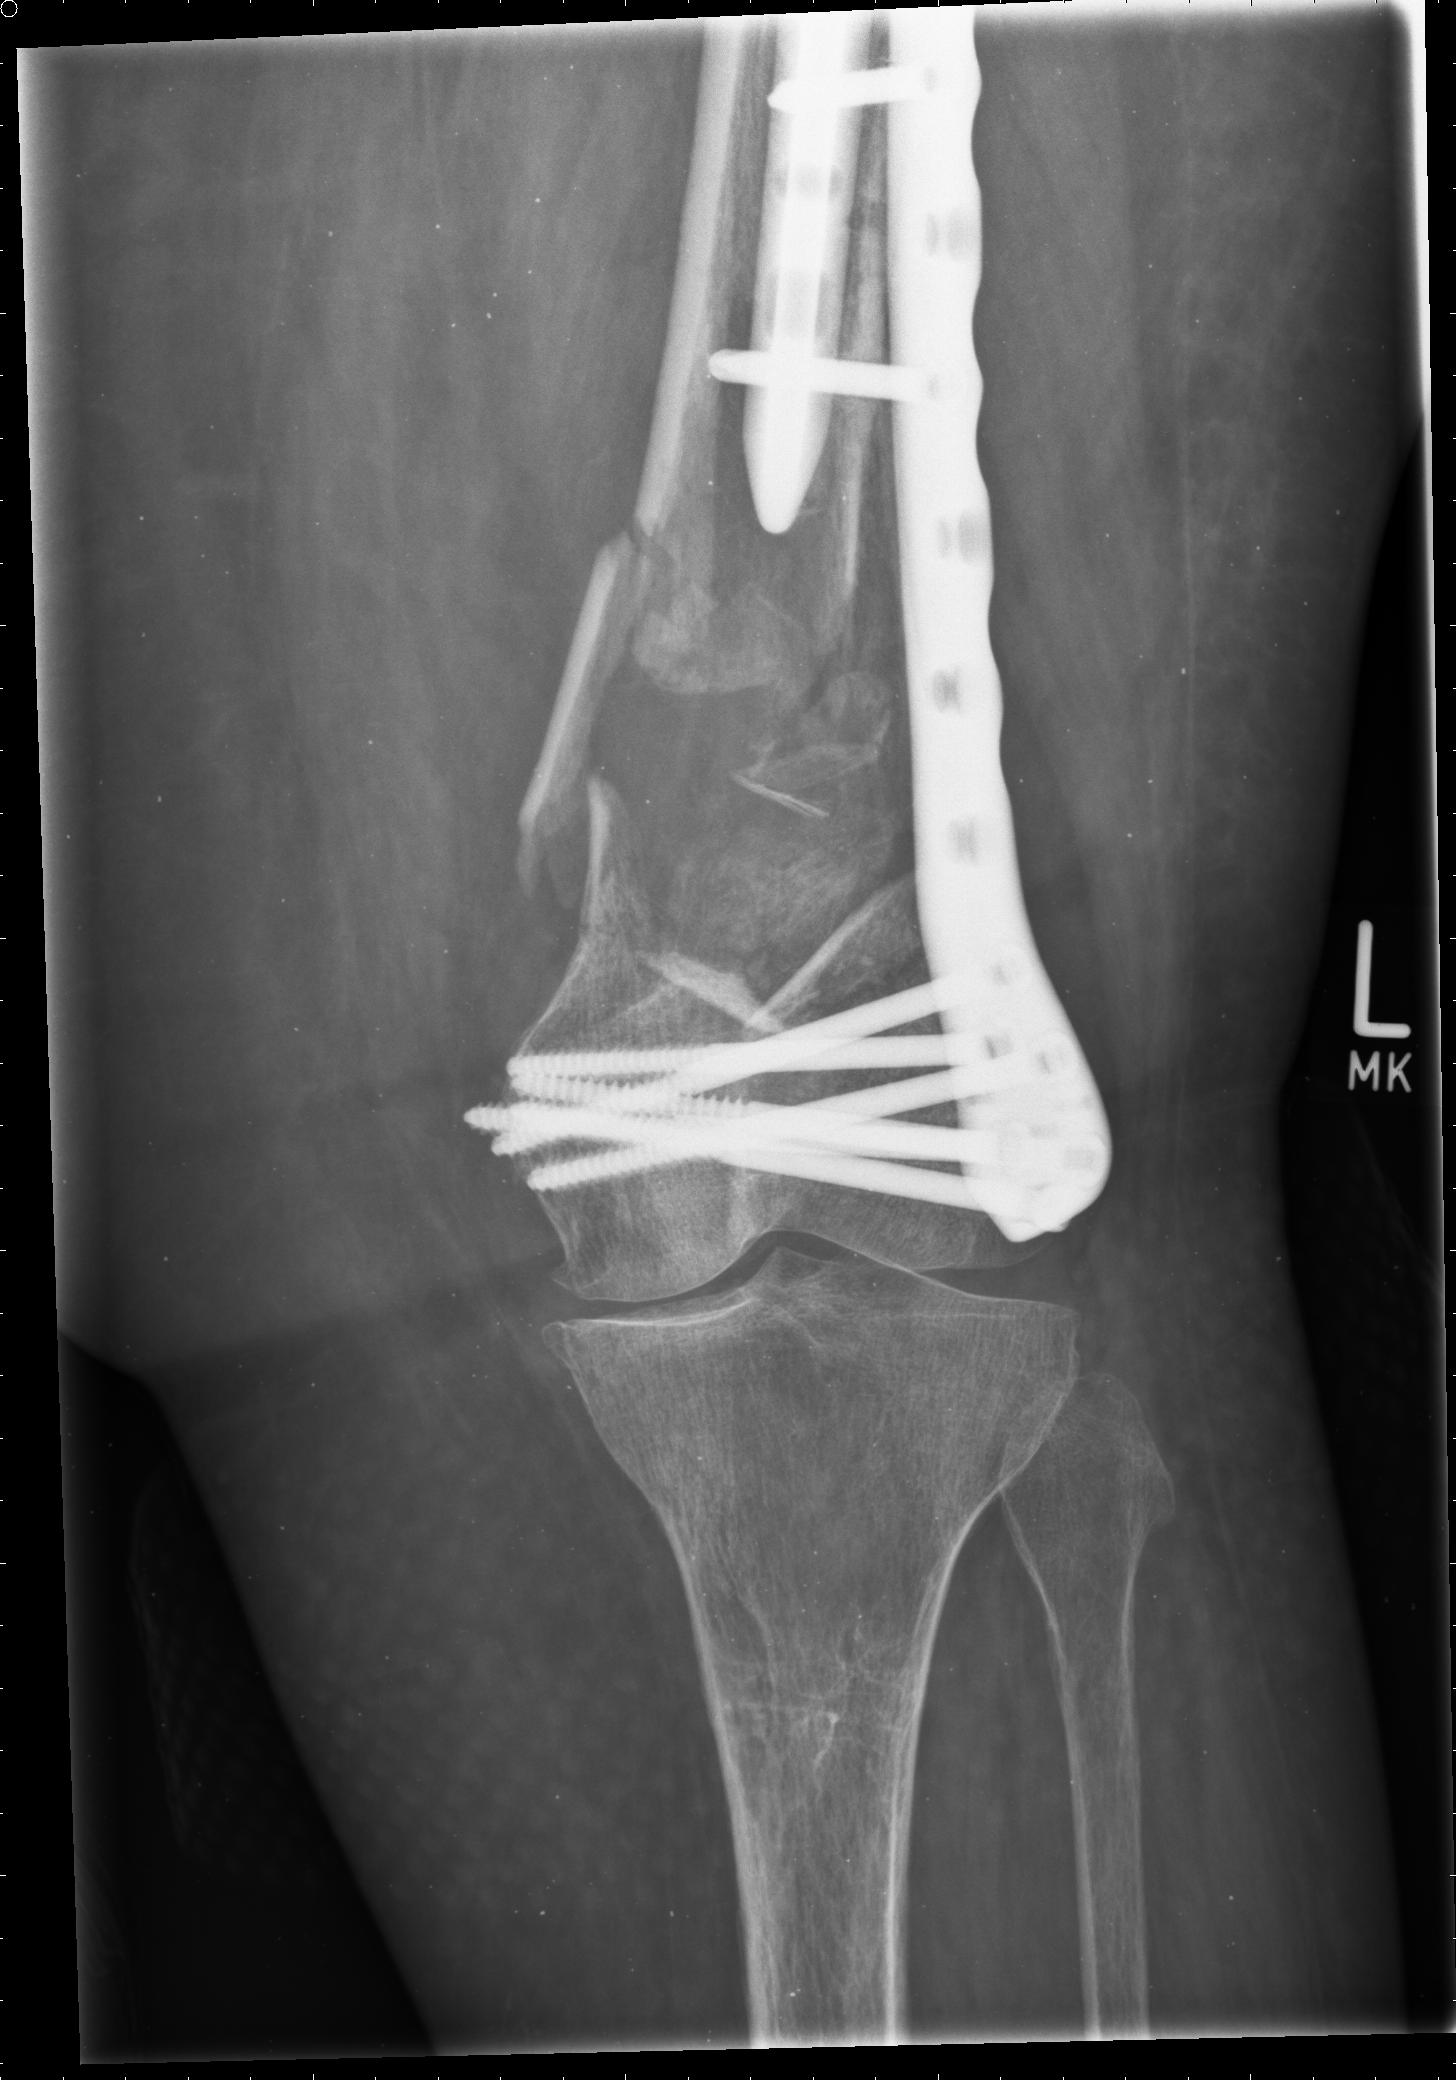

This 81 year old patient suffered from a Vancouver C ; OTA 33 A1 fracture pattern.

The fracture was reduced and fixed in a mini open technique by cerclage and an NCB Distal Femur plate. In the presented case the plate could have been longer in order to overlap the stem of the hip prosthesis at minimum 3-4 cm. Nevertheless the fracture healed uneventfully.